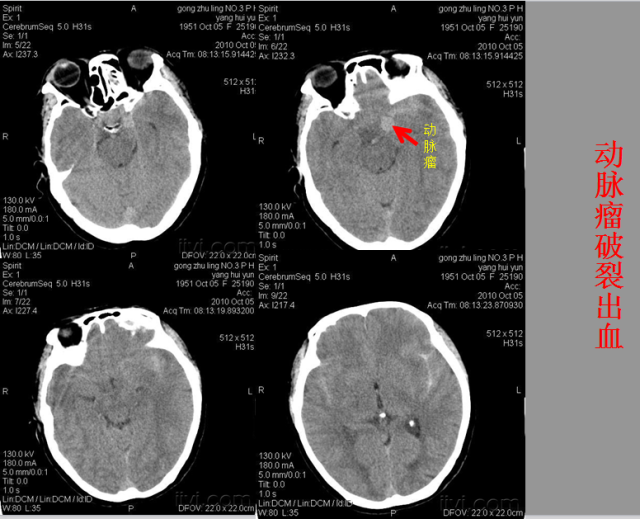

急性颅脑损伤篇

急胸症篇